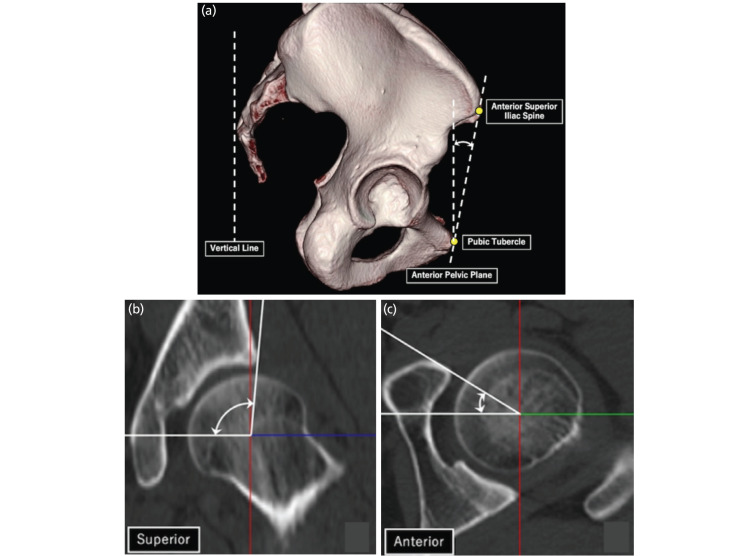

Materials and methods: This retrospective study included 57 patients with DDH (77 hips) who underwent PAO (DDH group). The control group comprised 30 patients (30 hips) with unilateral femoral head necrosis and contralateral unaffected hips (healthy hips). Coronal planes were created parallel to the femoral neck axis based on three-dimensional image analysis of hip computed tomography images. Coronal slices were obtained using clockwise rotation around the femoral neck axis in 15° increments, creating seven positions for measuring alpha (α)-angles. The superior and anterior directions were defined as 12 o'clock and 3 o'clock, respectively. Cam deformity was defined as an α-angle ≥60°. Outcome measurements were the α-angles of seven slices, cam deformity, and correlations between the maximum value of the α-angles and related factors.